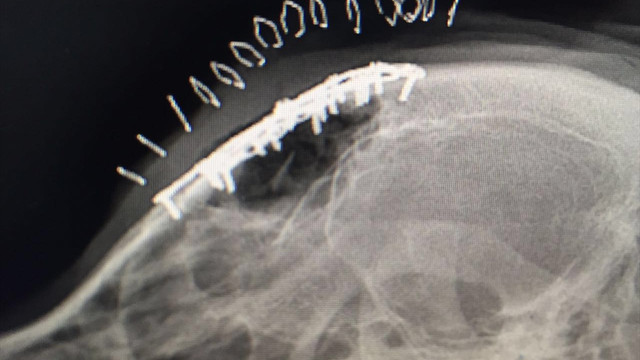

Köpeğin yapılan muayenesi ve çekilen radyografisi neticesinde travmaya bağlı alın kemiğinin çok parçalı kırığı ve buna bağlı sağ ve sol frontal sinusta çökme olduğu belirlendi.

Büyük bir alanda meydana gelmiş çok parçalı kırık ve çökme hattı, Prof. Dr. Kemal Altunatmaz tarafından uzun ve başarılı bir operasyonla plaka uygulanarak düzeltildi.